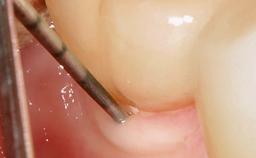

Paolo Casentini and Matteo Chiapasco present a case in which the peri-implant defect was not suitable for a fully regenerative approach. It involves implant removal, use of a CAD/CAM customized titanium mesh in the grafting phase, and placement of new implants. A 62-year-old woman was referred for consultation regarding her implant-supported prosthesis replacing teeth 14 to 16. The patient’s main concern was pain and recurrent swelling in the right posterior maxilla. The patient also reported difficulty and discomfort when brushing the area. The patient reported she had been treated in another country, where she had received three implants in combination with sinus-floor augmentation for the replacement of the posterior maxillary teeth three years earlier. The patient indicated “endodontic complications” to be the reason for the extraction of the teeth.